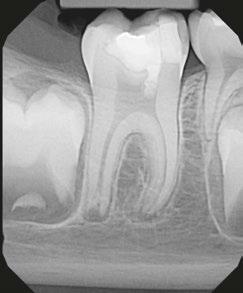

My first “ah-ha” moment came when I saw the closing of a long-standing large sinus tract on my pediatric 8-year-old patient, who after trauma presented with chief complaint of mobility, swelling, and likely a situation that looked hopeless. The biggest challenge with an open apex case is productive disinfection followed by creation of a long-lasting seal. Calcium hydroxide was used as the intracanal medicament between visits. Because it was not radiopaque, it was hard to gauge if it even made critical contact with the periradicular biofilm. I placed a CollaPlug® scaffold gingerly, visualizing with the microscope and then placed the MTA on the CollaPlug pillow taking several radiographs until I felt that I could see the MTA appear to encapsulate the irregularly shaped apex. Despite the visually satisfying post-op radiograph, I would come to see the amazing periapical healing complete with a rejuvenation of the periodontal ligament and concomitant osseous healing.

I don’t remember the first time I actually used MTA for an apexogenesis in my private practice, but the circumstances were always the same. I would get a call regarding a fracture to a front tooth with a pulp exposure on an 8-year-old child. If I couldn’t see that child that day, I would instruct my referring dentist to gently cover the pulp exposure with GIC and refer to me ASAP. The protocol required removing a minimum of 2 mm of pulp tissue or until any bleeding stopped. I would use a diamond in a high speed with copious irrigation. Gently disinfecting with chlorohexidene and placing a saturated cotton pellet to assess healthy pulp was critical followed by placing a 2 mm thickness of MTA as a direct pulp cap. In those days, I would place a wet cotton pellet on top of the MTA and seal with Cavit™ per manufacturer’s recommendations. I would then bring the patient back to confirm set of the MTA, absence of symptoms, and do the definitive coronal restoration.

Whether it was a traumatic pulp exposure or a carious pulp exposure on an asymptomatic child with under developed roots, I was seeing consistent success. The patient was remaining asymptomatic because the pulp vitality and health was maintained. I was further rewarded with being able to see that beautiful dentin bridge that developed underneath the MTA protecting that healthy pulp as the root grew in length and closed.

With trauma protocols, we recall these patients quarterly for the first year prepared to intervene with traditional endodontic treatment anytime we see evidence of failure. We then see these patients annually for 5 years, or more often, until I am satisfied that the root growth is complete. Unfortunately, I was starting to see an ugly silver gray halo at the cervical margin as a result of the tooth erupting out of the alveolus as part of the normal growth of the child. All of a sudden, I was faced with another treatment challenge. Now I had to take out my minimalistic composite, remove MTA, and then remove tooth structure to facilitate non-vital bleaching. I remember being very frustrated that we were weakening tooth structure coronally after working so hard to grow the root. I also faced the possibility of damaging the pulp as we had to remove much of that 2 mm MTA cap.

Figures 1 and 2: Example of staining from traditional MTA, non-vital bleaching after Figure 3: Pre-op Figures 4 and 5: Pulp cap Figures 6: Apexogenesis